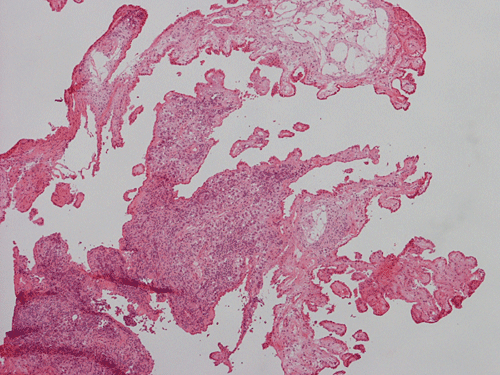

Pathology of the Case: The sample submitted for frozen section has a papillary structure which can be identified as the choroid plexus (Panel C). The center of the choroid plexus is expanded by some large cells accompanied by some smaller cells presumably lymphocytes (Panel D and E). On hematoxylin and eosin stain of the permanent sections, the tumor is composed of clusters of large cells in a background of lymphocytes. On higher magnification, the large cells have enlarged nuclei with prominent nucleoli. No trophoblasts or nor seminomatous component are identified. Immunohistochemistry demonstrated strong positive reactivity for placental alkaline phosphatase (PLAP) (Panel I) and CD117 (c-kit) in the large atypical cells (Panel J). The lymphocytes in the background are strongly immunoreactive for leukocyte common antigen (LCA) (Panel K) but negative for PLAP and CD117.

Typical diagnostic workups should include a CSF study for the tumor markers human chorionic gonadotropin (β-HCG) and alpha fetoprotein(AFP), but in most cases stereotactic biopsy is needed for diagnosis 5. Endoscopic biopsy typically yield a minute specimen which may not be representative of the tumor. With this token, the biopsy specimen may appear purely seminomatous but non-seminomatous component may be present in the tumor but not represented in the biopsy specimen. Serum markers help to detect these tumors. Markedly elevated levels of β-HCG usually indicate the presence of choriocarcinoma, while elevated levels of AFP indicate an endodermal sinus tumor.  Mildly elevated levels of β-HCG are less specific, and could be seen in all types except teratomas. These serum markers are also helpful in the detection of tumor recurrence.